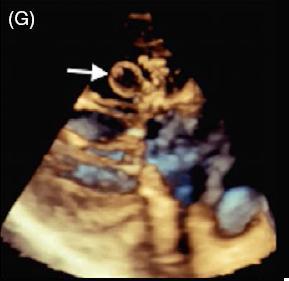

患者女,42 岁,以「急性视网膜动脉闭塞」病史就诊,既往无慢性疾病。经胸超声心动图检查发现二尖瓣后叶可见一囊状结构,可活动(图 A 和 B)。二维和实时三维经食管超声心动图检查显示一柔软的圆形结构附着于二尖瓣后叶,活动性良好(图 C ~ G)。主动脉弓、左心房、左心耳和左心室均正常。根据病变形态特征及超声表现,诊断为二尖瓣附瓣。其它影像学检查如 MRI、颈动脉多普勒超声均无异常。基于上述检查结果,考虑急性视网膜动脉闭塞为 AMVT 所致,建议外科手术切除二尖瓣附属组织,但是患者拒绝,选择随访观察。

图 C~F 二维经食管超声心动图显示一柔软的圆形结构附着于二尖瓣后叶,活动性良好